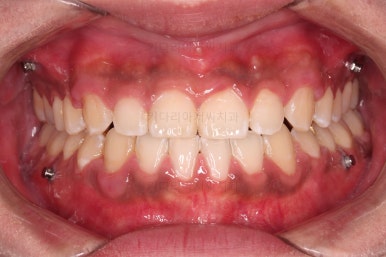

가지런한 느낌, 앞니 뻐드러짐을 좋게 했고요.

교합도 맞춰 위아래가 톱니바퀴처럼 맞물리게 했고, 앞니도 위아래 관계를 잘 맞추고 마무리를 했습니다.

전후 비교해 볼게요.

1년 3개월이라는 비교적 짧은 기간안에 적절한 교합, 심미성 등 여러 가지를 달성했던 만족스러운 치료였습니다.

이상 비수술, 비발치로 주걱턱 및 앵글씨 3급 부정교합을 개선했던 부산교정 치료사례였습니다.